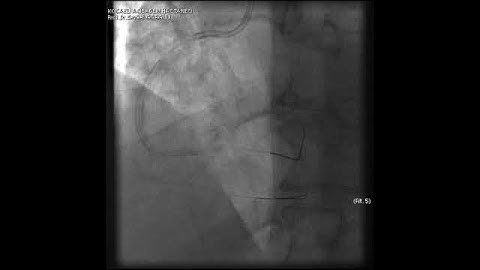

Complex PCI for RCA CTO with bifurcation at distal cap video 1